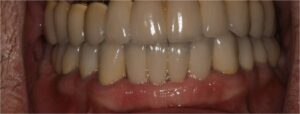

- Ακινητη προσθετικη, δηλαδη στεφανες και γεφυρες

- Προσθετικη επι εμφυτευματων